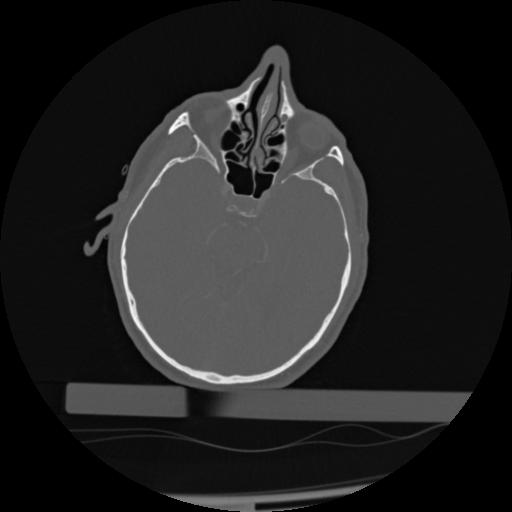

22 ANGIO,CE,Vol,0.5,ANGIO,,